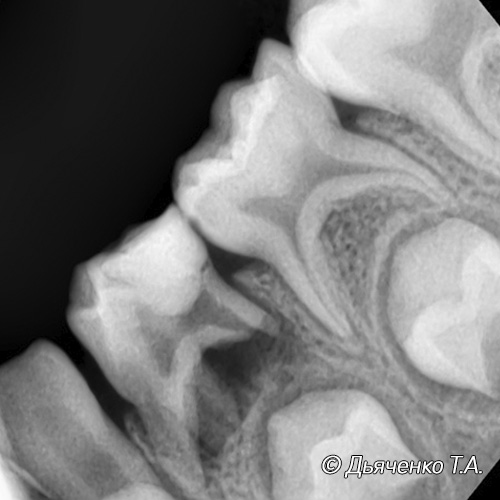

Если помощь ребенку не оказана, далее инфекция начинает распространяться из полости зуба в корневые каналы. Разрушается ткань сосудисто-нервного пучка (пульпы), воспаление при длительном течении приводит к отмиранию (некрозу) тканей. Все это может способствовать развитию периодонтита либо в хронической форме, либо острой в результате гнойного расплавления пульпы.

Острый периодонтит возникает, когда скопившийся экссудат не находит выхода. Десна в области зуба краснеет и опухает. Может подняться температура тела. Ребенок плачет, отказывается от еды, нарушается сон и поведение малыша.

Длительный хронический периодонтит, острый периодонтит молочного зуба часто являются следствием обширного воспаления, ранней инфекционной резорбции корней молочных зубов более чем на ½. Все это является показанием к удалению таких зубов. При остром процессе удаление может быть сочетано, строго по назначению врача, с приемом медикаментозных препаратов (антибиотики, антигистаминные препараты и т.д.).